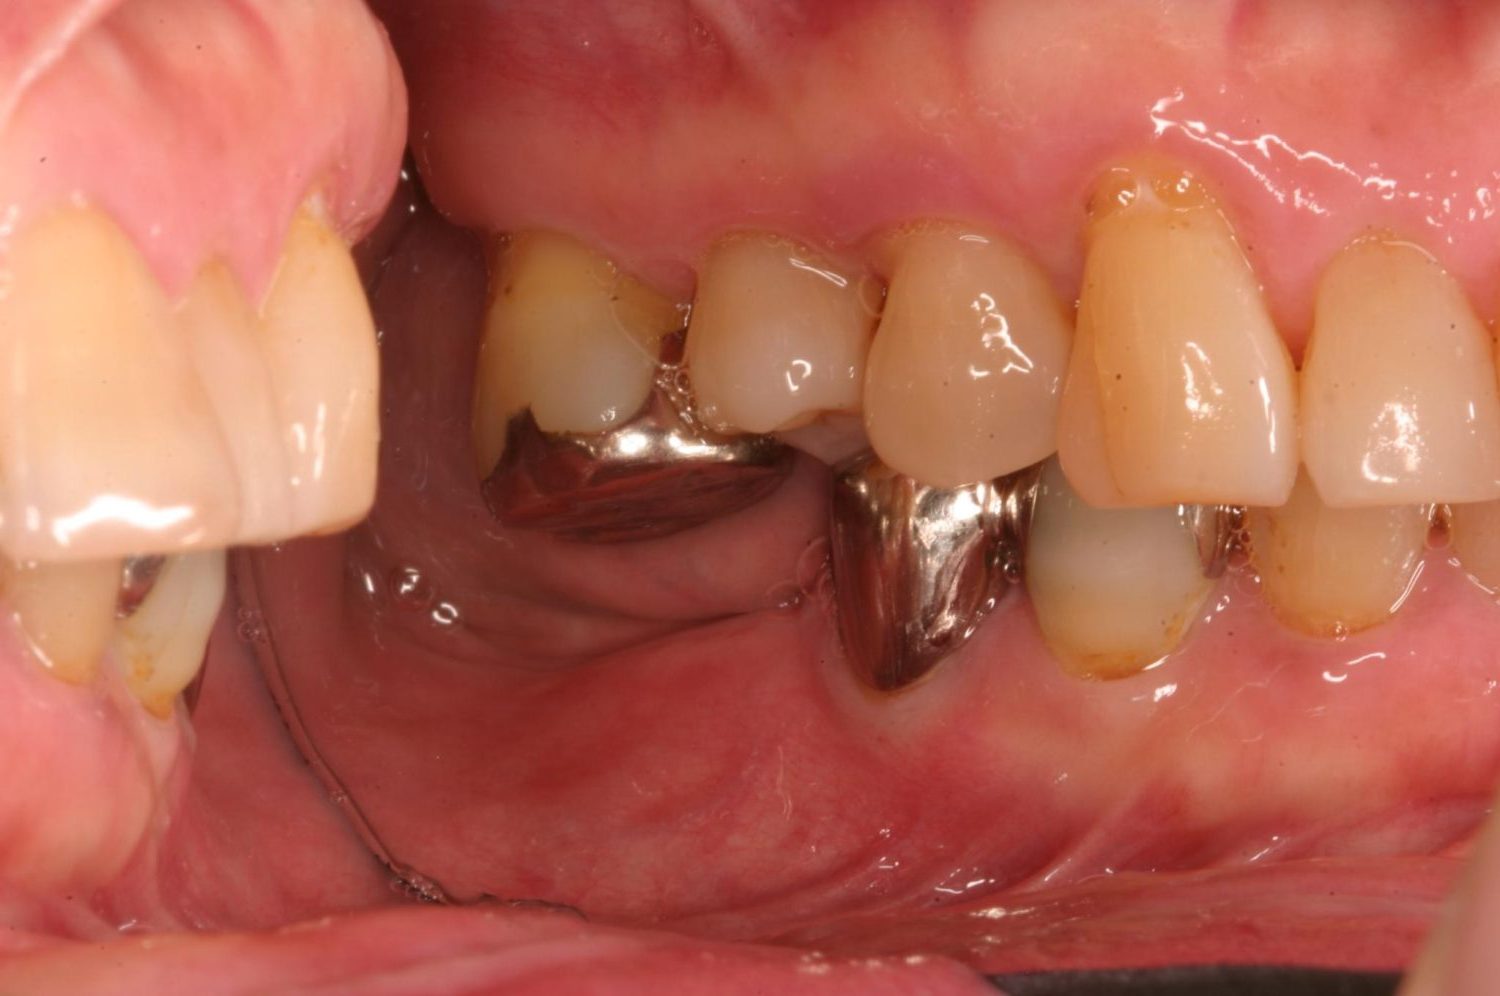

インプラント治療の症例紹介④

Before

After

主訴

義歯による疼痛

治療内容

下顎舌側に骨隆起があり義歯困難な状態。保存不可能な歯の抜歯を行い、インプラントを埋入し咬合再構成を行った。

治療費

2,851,200円(税込)

治療期間

29ヶ月

通院回数

26回

想定されたリスク

※咬合力の強い方なので、予防的にマウスピースの装着が必要。インプラント周囲炎の恐れがありました。

歯の欠損の対合歯の挺出等を修正し咬合平面を揃え咬合再構成を行った症例。